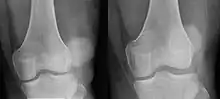

![]() | |

| Patellar luxation on radiograph: Left before, right after reduction; after reduction, the patella is still displaced. | |